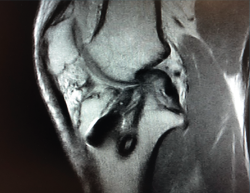

El tratamiento de un paciente que sufre una rotura aguda del LCA (Figura 2) sigue siendo motivo de discusión(9). Hay muchos condicionantes que influyen en el manejo terapéutico de estas lesiones (ya sea quirúrgico como no quirúrgico), como son la edad, la ocupación, la actividad deportiva, las lesiones asociadas, el grado de laxitud de la rodilla, las expectativas o las recidivas de la lesión, entre otras. El riesgo de artrosis tras la rotura aguda del LCA será mayor en ambos grupos con respecto a la población sana, sea cual sea el tratamiento(12). Los factores de riesgo más importantes para el desarrollo de artropatía son: lesión meniscal, meniscectomía e injerto hueso-tendón-hueso (HTH).

Figura 2. Rotura aguda del ligamento cruzado anterior.